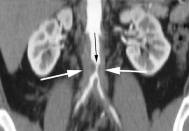

Aortna insuficijencijaU akutnoj aortnoj insuficijenciji zbog nemogucnosti adaptacije LK, UV pada uz dramaticno visok enddijastolni pritisak (I preko 40 mmHg)U ch. AI efektivni UV i EF su normalni / neznatno smanjeni i u miru i pri naporu.EF LK odrzava se normalnom cak i kada pocne depresija miokardne funkcije (procenjena na osnovu nagiba krive ESP/ESV kao najosetljivijeg funkcionalnog pokazatelja). Sa napredovanjem disfunkcije LK , EF pri naporu pada,a ESV raste I bez dodatnog povecanja RV.ESV se uzima kao sveukupan indeks miokardna funkcije LK I dobro korelise sa operativnim mortalitetom I sa dugorocnom prognozom.Ishod je bolji ako je ESV manje od 40ml/m2 ,a los ako je ESV veci od 80ml/m2.Umesto ESV mnogo cesce se ehokardiografski odredjuje ESD LK.Granicna vrednost u pogledu reverzibilnosti disfunkcije LK je ESD najvise 5,5 cm.